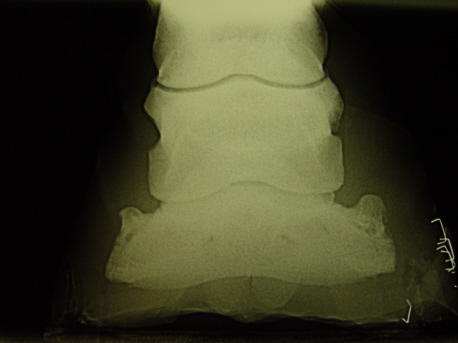

AP Aufnahme

Flaches atrophiertes Hufbein